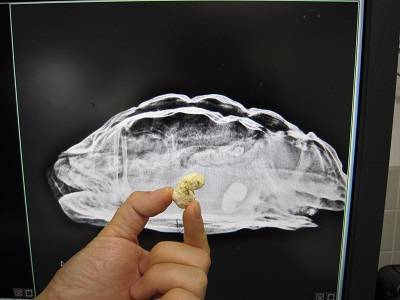

先ほどの結石と見比べてみると・・・

似たような形ではありませんか?

ちなみにカメのレントゲンは、このように

上から

横から

前から

と3方向から撮ることが多いです。

例えば今回の結石のようなものが、体のどの位置にあるのかもこれで把握できます。